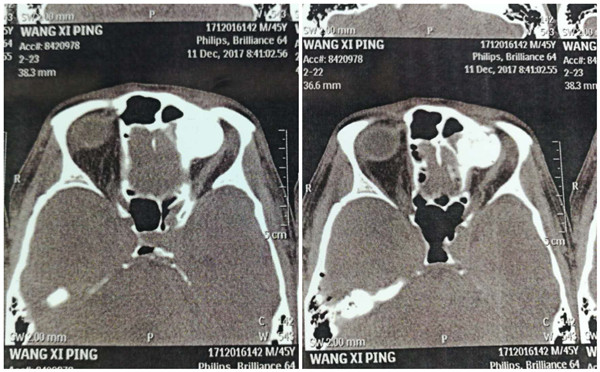

患者王某某,男,45岁,以“左额部胀感、左眼视力下降2年”之主诉入院。患者近2年前曾行外径路骨瘤切除术,术后患者再次出现左额部胀感、左眼视力下降。在我院就诊后,行鼻窦CT发现骨瘤位于左侧眼眶周围,范围较大,肿瘤向下压迫眼球致其移位。考虑到手术的微创性及患者对面部美观性的要求,汪立副主任医师和祝康副主任医师鼻科团队,决定在鼻内镜下施行额窦骨瘤切除术。由于骨瘤位置较高,凸入眼眶引起压迫的部位位于眶上壁,手术操作十分困难。汪立副主任医师和祝康副主任医师相互协助,借助精良的手术器械及良好熟练的鼻内镜手术技术,历时5小时,顺利将骨瘤切除,缓解了患者眼眶的压力。

术后术前对比